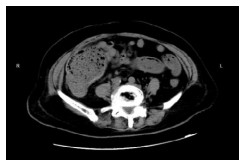

1 资料与方法病例1,患者女,72岁,2020年9月2日因“腹痛3 d”来本院急诊,拟“升结肠肿瘤伴肠梗阻”收住院。半月前因“胆囊结石”在当地医院行腹腔镜下胆囊切除术。本次入院查体:腹部膨隆,右下腹部压痛明显,轻度反跳痛。WBC13.3×109/L, N 84.0%。腹部增强CT提示升结肠管壁不规则增厚伴管腔狭窄,回盲部及远端回肠扩张明显(图 1)。肠镜检查:升结肠肿物,予取病理活检后,在肠道狭窄处行肠梗阻金属支架植入解除梗阻(以维持肠腔的通畅性和减少肠道毒素的进一步吸收)。肠镜病理提示:(升结肠)管状绒毛状腺瘤,部分高级别上皮内瘤变。3 d后复查腹部平扫CT示回盲部及远端回肠原先扩张的肠腔已明显缩小(图 2)。因患者既往有糖尿病史,时常合并胸闷胸痛,心电图示侧壁T波直立,心内科会诊建议行心脏冠脉造影。冠脉造影提示心脏左前降支中段狭窄约百分之八十,远端约百分之九十狭窄。经多学科讨论后认为患者目前急性肠梗阻症状已经缓解,建议可先予冠状动脉药物涂层支架植入术,再予以替格瑞洛口服抗凝治疗,1个月后再次入院行结肠肿瘤手术。患者于2020年10月9日再次入院行腹腔镜下右半结肠癌根治手术,手术过程顺利。术后病理报告:(升结肠)高-中分化腺癌,T3N1M0。患者术后13 d出院,并接受了后续的规律化疗。目前患者恢复良好。

| 图 2 放置升结肠支架3 d后复查腹部平扫CT示回盲部及远端回肠原先扩张的肠腔已明显缩小 |